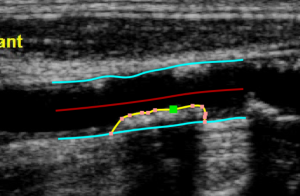

The Trace borders  button is used to manually trace the borders of the vessel. The user has to trace point-by-point the vessel edges and the software interpolates them. It is possible to modify the points by dragging them, as shown in the following picture.